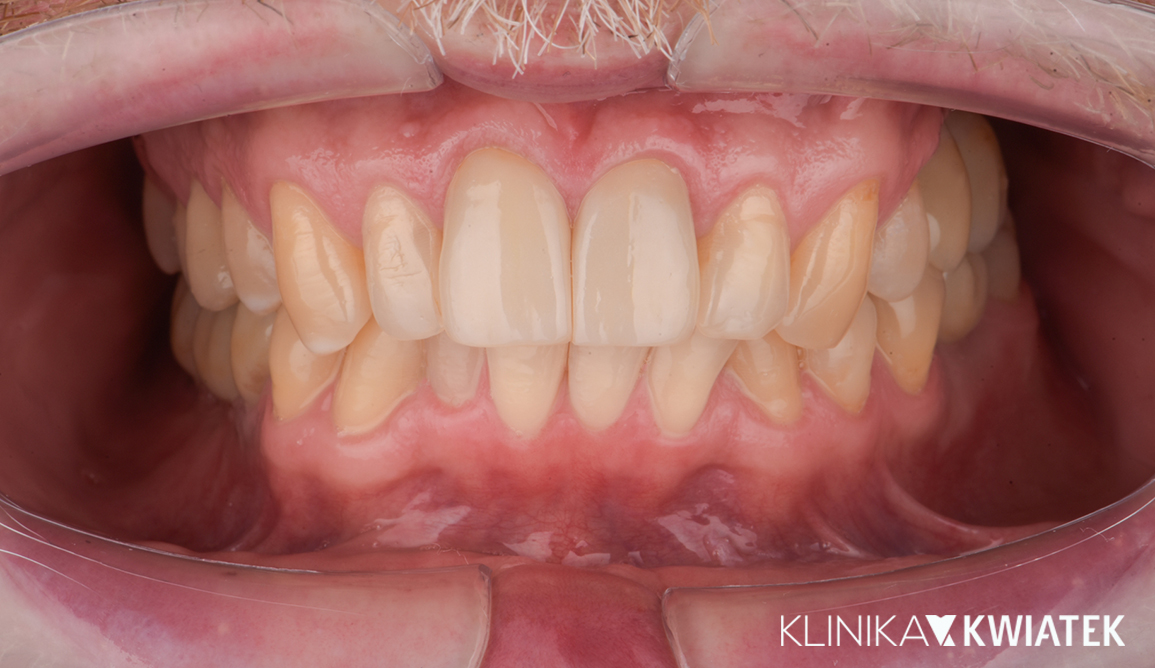

PRZED

PO